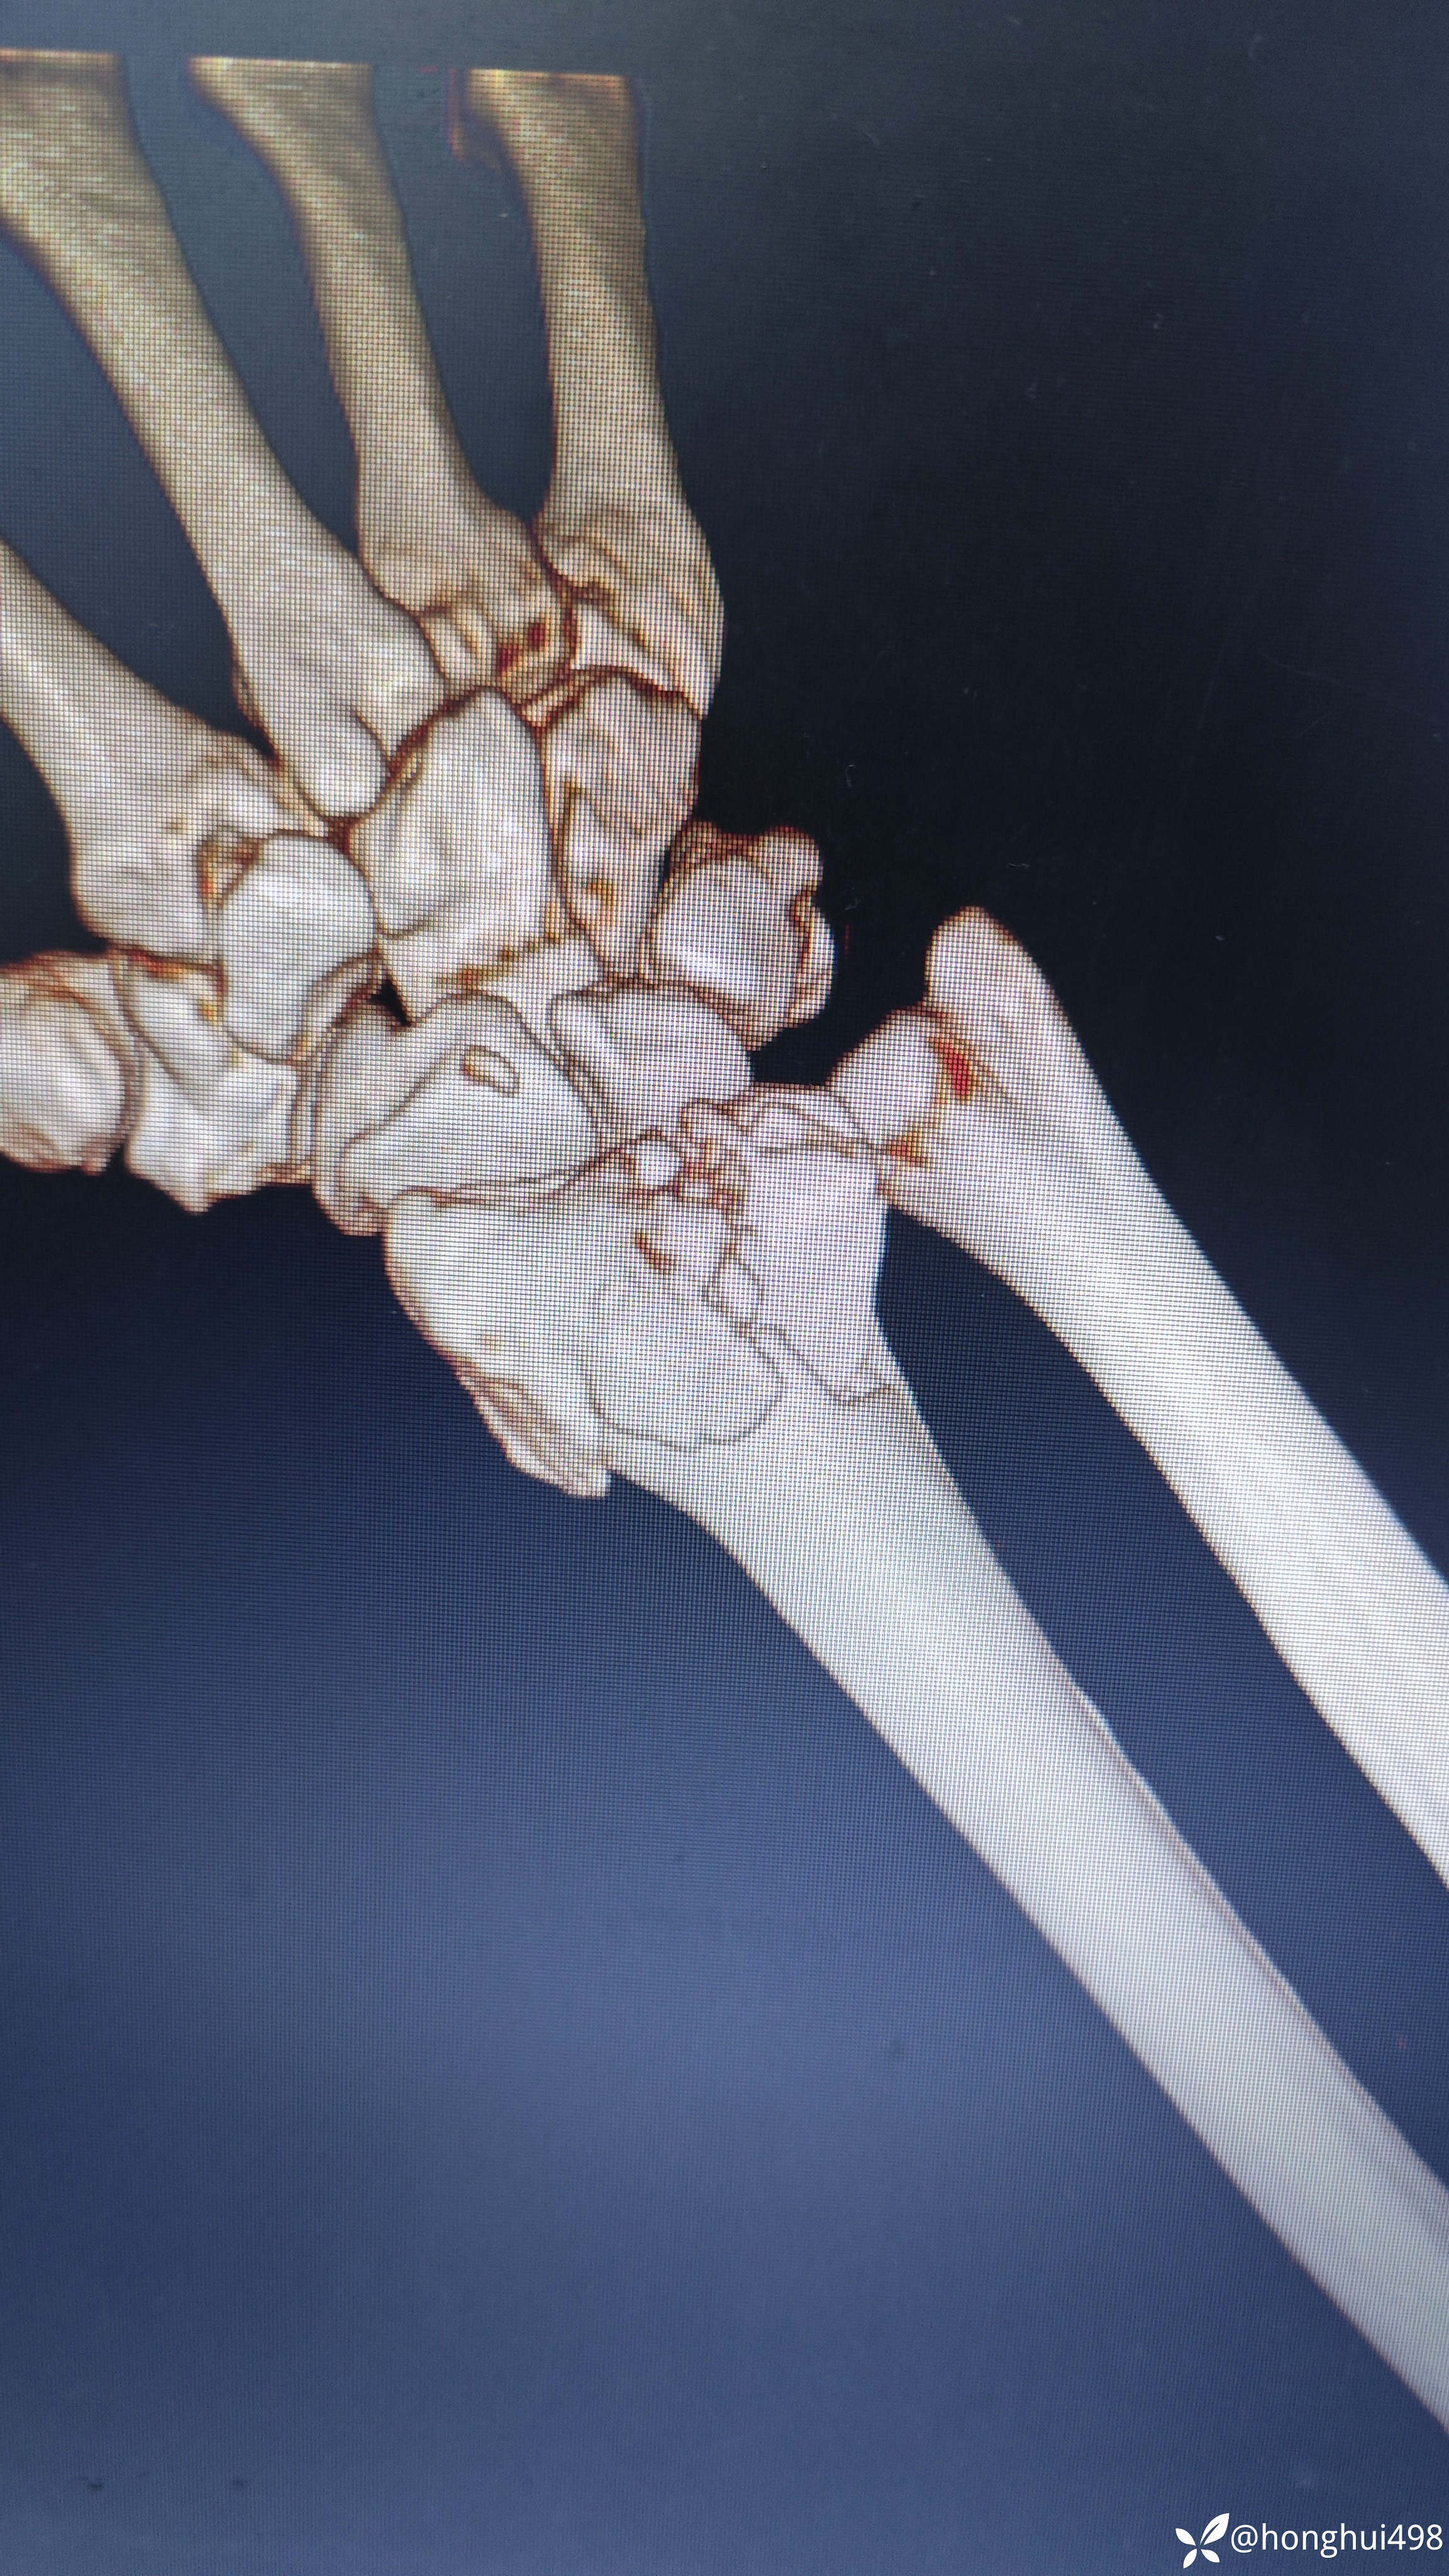

女性患者,49岁,因在家行走不慎滑倒受伤,右腕部畸形,肿痛活动受限1小时入院。入院诊断:右桡骨远端骨折。尝试手法整复失败,臂丛麻醉下行切开复位钢板内固定术。

术后复查结果